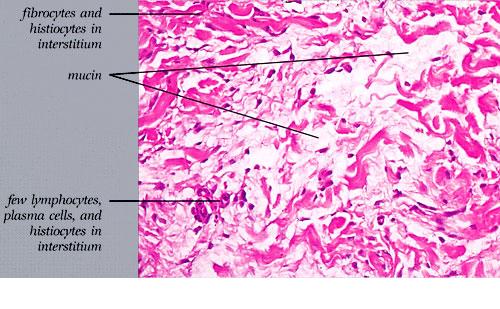

The mucin found in these six diseases represents an increase in the mucin that is normally present in the ground substance of the dermis. It consists of proteins bound to hyaluronic acid (hyaluronan), which is an acid mucopolysaccharide or glycosaminoglycan. As a result of the great water-binding capacity of hyaluronic acid, dermal mucin contains a considerable amount of water. This water is largely removed during the process of dehydration of the specimen; consequently, in routine sections, the mucin, because of its marked shrinkage, appears largely as threads and granules.

The mucin present in the six types of mucinosis stains a light blue in sections stained with H&E. It also stains with colloidal iron. It is Alcian blue-positive at pH 2.5 but negative at pH 0.5 and shows metachromasia with toluidine blue at pH 7.0 and 4.0 but no metachromasia below pH 2.0 . It is PAS negative (indicating the absence of neutral mucopolysaccharides) and aldehyde fuchsin negative (indicating the absence of sulfated acid mucopolysaccharides). The mucin is completely removed on incubation of histologic sections with testicular hyaluronidase for 1 hour at 37"C .